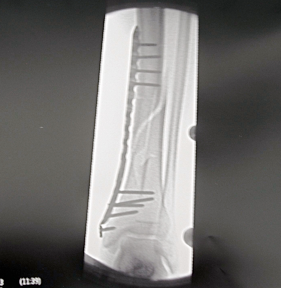

En este caso se presenta una fractura de Tibia que sufrió un motorista al ser arrollado por un coche.

Con una suave tracción y manipulación de la pierna, se ha conseguido alinear la fractura. A pesar de esta magnifica reducción de la fractura, si se mira con detenimiento las imágenes, se pueden apreciar pequeños fragmentos óseos que están muy lejos de su sito y varios trazos diferentes de fractura (una linea con forma espiroidea y otra con forma longitudinal, además del defecto que ha dejado un fragmento triangular)

La fractura no es simple, pero se ha conseguido un magnifico alineamiento de la fractura al manipular la pierna. Por lo que decidimos operar y fijar la fractura siguiendo una de las procedimientos mas modernos hoy en día:

Se realiza una pequeña incisión sobre la cara interna del Tobillo y bajo control de Rx insertamos una placa de Titanio siguiendo el trayecto ascendente de la Tibia.

Con minúsculas incisiones sobre la piel se insertan varios tornillos para fijar las dos partes de la Tibia en su correcta alineación.

Resultado Postoperatorio:

Al terminar la operación, se comprueba el resultado con una radiografía.

En la Rx, se puede apreciar el gran tamaño de la placa y la tornillería que hemos introducido a través de una mínima exposición, menor de 3 cm.

Una placa de este tamaño es necesaria para poder soportar las cargas que se producen en la pierna al apoyar, de tal forma que el paciente puede comenzar a caminar con ayuda de muletas, desde el día siguiente a la operación.